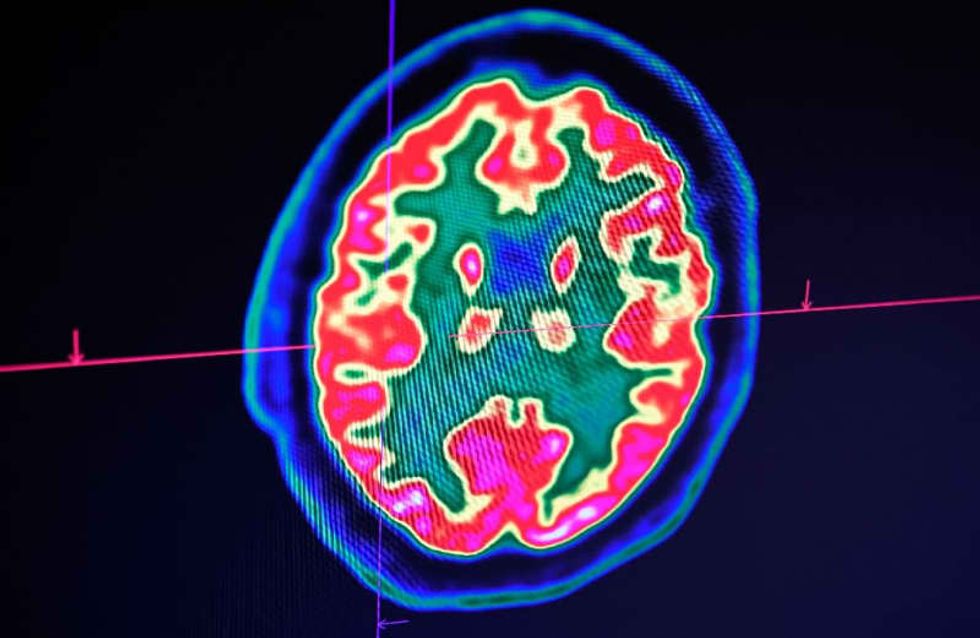

Washington (AFP) - A pattern is emerging among COVID-19 patients arriving at hospitals in New York: Beyond fever, cough and shortness of breath, some are deeply disoriented to the point of not knowing where they are or what year it is. At times this is linked to low oxygen levels in their blood, but in certain patients the confusion appears disproportionate to how their lungs are faring.Jennifer Frontera, a neurologist at NYU Langone Brooklyn hospital seeing these patients, told AFP the findings were raising concerns about the impact of the coronavirus on the brain and nervous system.By now, mo...